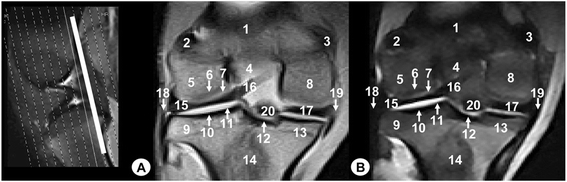

Dorsal MR images of stifle joint. Cranial view. Line depicts the section at the level of the transverse ligament of stifle. a SE T1-weighted MR image and b GE STIR T2-weighted MR image. 1. Femoral metaphysis, 2. Lateral femoral condyle, 3. Cortical bone of the femur, 4. Articular cartilage of the femur, 5. Intercondylar notch of femur, 6. Medial femoral condyle, 7. Lateral tibial condyle, 8. Cortical bone of the tibia, 9. Articular cartilage of the tibia, 10. Medial tibial condyle, 11. Tibial metaphysis, 12. Lateral meniscus, 13. Medial meniscus, 14. Lateral collateral ligament, 15. Medial collateral ligament, 16. Cranial cruciate ligament, 17. Femorotibial joint (articular capsule), 18. Transverse ligament of stifle

On the MR images (Figs. 2, 3, 4, 5, 6, 7, 8, 9 and 10), anatomic details of Bengal tiger stifle joints were compared with the anatomical dissections and evaluated according to the signal intensity of the different bony components and soft-tissues structures. Several structures of femorotibial joint were clearly visible with low-field MRI. Therefore, on SE T1-weighted sequences, the signal intensity of the cortical and subchondral bone of the femur and tibia was lower compared with the high signal intensity of the trabecular bone. However, on GE STIR T2-weighted MR images, the trabecular bone appeared with low signal intensity, as well as by observing the area of negligible signal corresponding to the cortical and subchondral bone of those bones. The articular cartilage of the femur and tibia was visualised with intermediate signal intensity in SE T1-weighted sequences, compared with GE STIR T2-weighted sequences where they showed high intensity signal. In both sequences, the signal of the articular cartilage was differentiated from trabecular bone by a dark line that corresponded to the subchondral bone (Figs. 2, 5, 6, 7 and 8). Articular capsule, menisci and ligaments were also seen with low signal intensity in both sequences. The synovial fluid could be identified in the articular cavity with intermediate signal intensity on the T1-weighted MR images. However, this fluid showed high signal intensity in GE STIR T2-weighted sequences.

The lateral and medial menisci were easily identified between the femoral condyles and the tibia as two triangular formations. These structures had low signal intensity in the sagittal (Figs. 2 and 5) and dorsal (Figs. 6, 7 and 8) planes, but they were not clearly observed in the transverse plane (Fig. 10). The meniscofemoral ligament was visible on the sagittal (Figs. 3 and 4), dorsal (Figs. 6 and 7) and transverse (Fig. 9) planes with low signal intensity. The cruciate ligaments were not completely distinguished in all three planes because of their oblique orientation and appeared with low signal intensity (Figs. 3, 4, 7 and 9). The lateral and medial collateral ligaments were well defined on the dorsal (Figs. 6, 7 and 8) and transverse (Figs. 9 and 10) planes as linear low signal intensity bands. These structures were difficult to differentiate to the cortical bone because of their similar signal intensity.